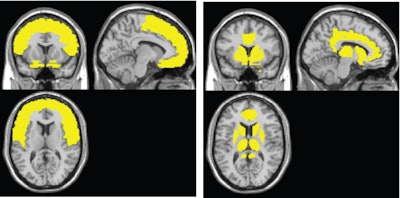

The group used MRI results to develop a two-stage model of the effects of HIV infection. First, the virus leads to atrophy in the frontal lobe, which links the brain's networks and controls executive and cognitive functions, beginning at the time of HIV infection. In contrast, damage to the caudate-striatum region, part of the brain's motor and reward system, becomes more evident when individuals develop clinical HIV-associated neurocognitive disorder symptoms.

The results suggest the use of a two-stage model to evaluate HIV-associated neurocognitive disorder in the context of brain atrophy. The first stage involves the frontal lobe, including the anterior cingulate cortex, while the second phase links HIV with neurocognitive impairment.

Through this model, the researchers determined that the frontal lobe is the most frequently affected brain region in HIV-positive adults, while the neural injury to the caudate-striatum area was consistently linked with neurocognitive impairment.